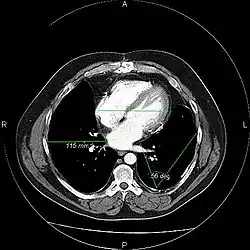

The same image following contrast adjustment, sharpening and measurement tags added by the system

An image as stored on a picture archiving and communication system (PACS)